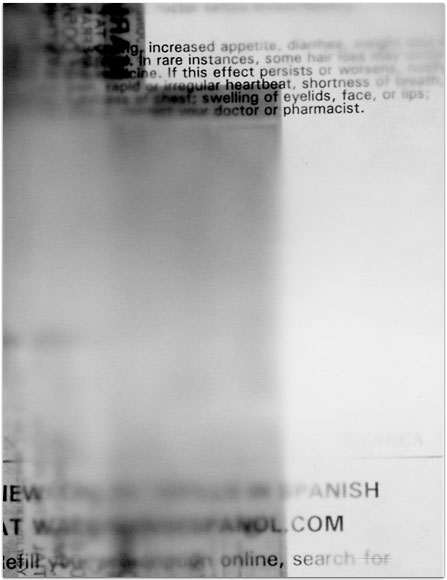

- Itis

- 2004

- 3.25″ × 4.25″

- Photographic montages of my hands & health paraphernalia on Polaroid Type 664 & 669 Film using a Daylab Printer.

- Frustrated by a lack of mobility and severe pain with my fingers, unable to accomplish any task requiring joint dexterity,

I noticed piles of health related papers strewn around. I layered these in a slide printer without removing

my hands, enlarging both onto the film.